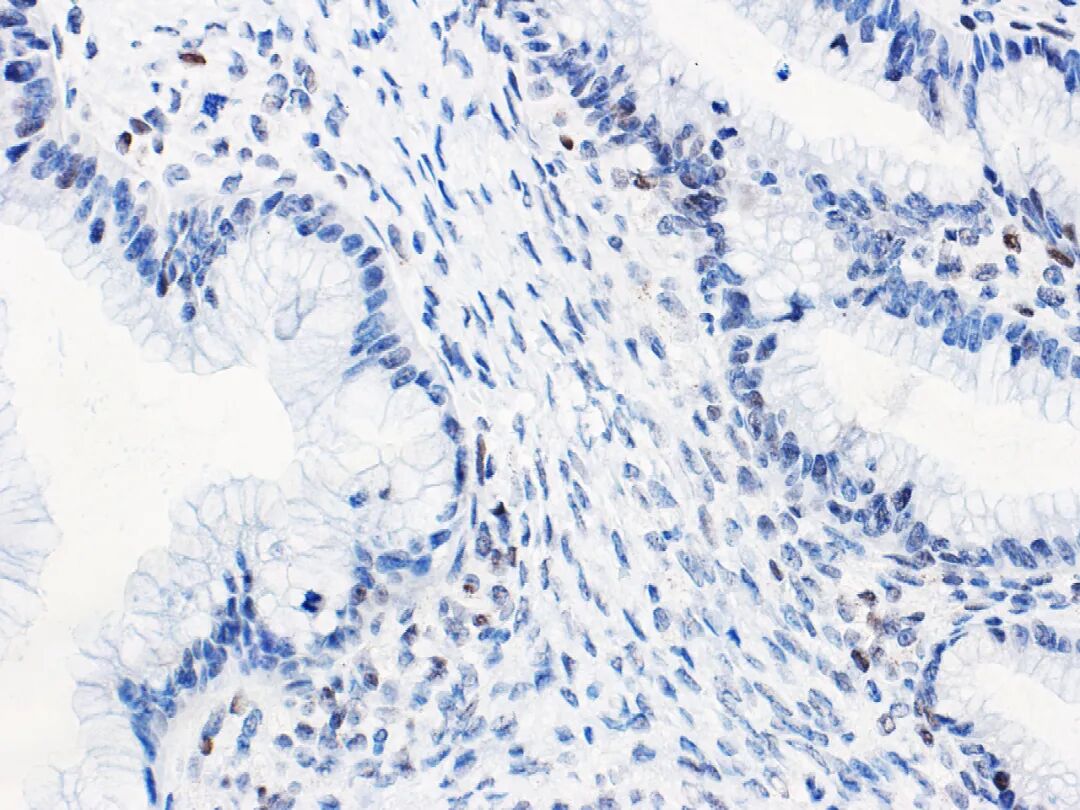

低级别浆液性癌的免疫组化p53多表达为野生型。但有少数病例具有取得性Tp53基因突变的报道,这类病例极为罕见,因此出现p53的异常着色模式通常不诊断卵巢低级别浆液性癌。这点在小的活检病例诊断中尤其重要,因为有些高级别浆液性癌由于呈微乳头状结构、细胞核为中等程度异型性,可能会类似低级别浆液性癌。需要注意的是有约2%的输卵管、卵巢高级别浆液性癌会有Tp53基因突变而其终止密码子超出了正常时候的位置,导致产生无功能的p53蛋白。因此,即使免疫组化p53表达正常的浆液性肿瘤也可能会是卵巢高级别浆液性癌,所以还是要结合形态学并建议加做必要的分子检测。有多家组织研究证实p53异常表达与卵巢子宫内膜样癌生存时间缩短有关。在I/IIA期卵巢子宫内膜样癌患者中也有类似结果。分期较低的卵巢子宫内膜样癌中,p53异常表达是可靠、强有力的生存预后指标。免疫组化p53结果预测卵巢黏液性肿瘤(如图3所示)中Tp53基因突变情况的准确性也比较高。表明Tp53基因突变与卵巢黏液性交界性肿瘤演进相关。顺利获得免疫组化方法来对大量卵巢黏液性肿瘤中p53的情况进行评估,未发现其结果与预后有关。然而,少量黏液性交界性肿瘤中的免疫组化p53结果与死亡风险增加有关。尽管对于这类患者的治疗方面方案有限,但免疫组化p53正常表达提示临床表现不同寻常的黏液性交界性肿瘤(如肿瘤破裂者)出现进展的风险较低。

图3.卵巢浆黏液样癌-野生型p53正常表达